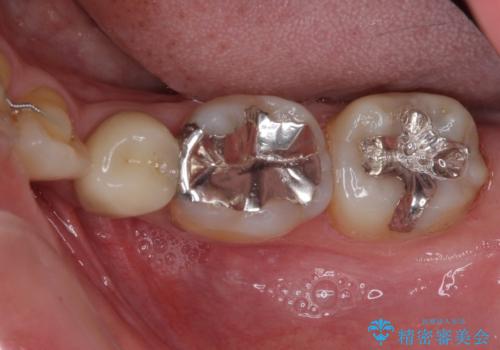

矯正治療後には、下顎臼歯の目立つ銀歯をセラミックインレーにて修復治療を行いました。

口を開けたときに金属が見えなくなり、患者様には大変満足していただきました。